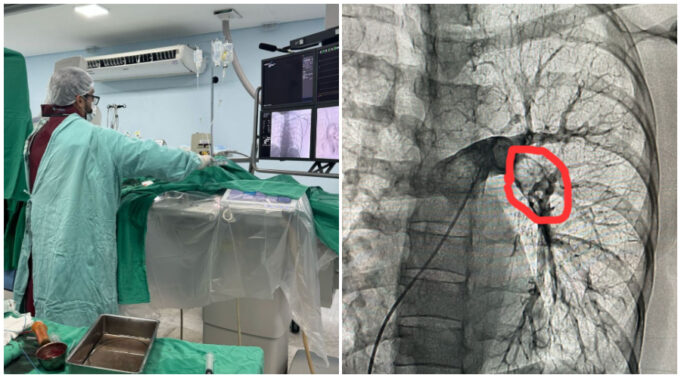

No último sábado, dia 22 de março de 2025, foi realizado mais um procedimento importante na hemodinâmica do Hospital Regional de Patos. Procedimento esse chamado Trombectomia Mecânica Pulmonar, que consiste na retirada mecânica de um grande trombo sanguíneo (coágulo) de dentro da artéria pulmonar (vaso que leva sangue para o pulmão).

O procedimento foi realizado em uma paciente de 50 anos, procedente de Patos-PB, que tinha sido recentemente submetida a uma cirurgia ginecológica, tendo evoluído com quadro de trombose pulmonar.

O procedimento foi realizado com sucesso, com a retirada pela hemodinâmica de grande quantidade da carga trombótica através da aspiração local do coágulo, melhorando assim o quadro clínico da paciente e diminuindo as pressões no leito pulmonar.